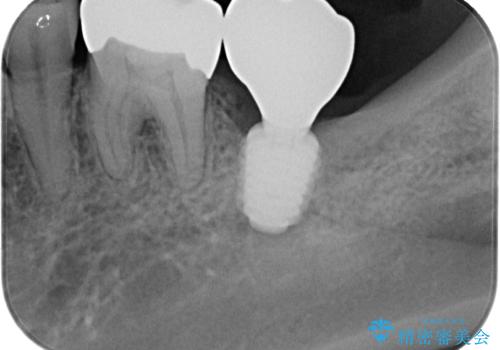

そこで今回は、抜歯即時インプラントの適応と判断しました。

抜歯と同時にインプラントを埋入し、さらにその日のうちに仮歯を装着することで、見た目と機能を即日に回復しています。

従来のインプラント治療では、抜歯からインプラント埋入まで数か月の待機期間が必要でしたが、抜歯即時インプラントでは1回の外科処置で治療が完了するため、